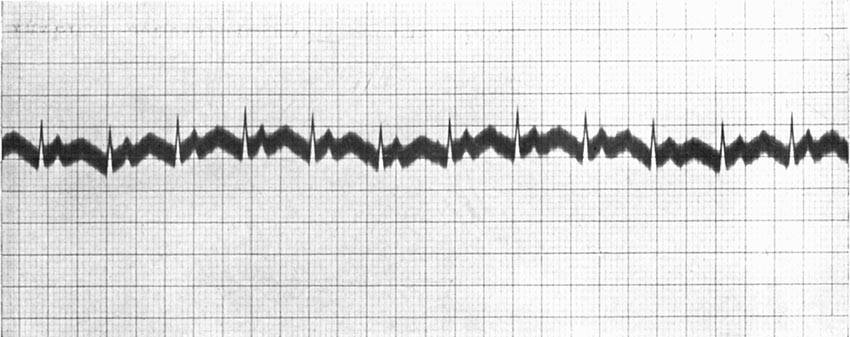

| Continuous Moving-picture Records of Heart-beats | 136 |

| Continuous Moving-pictures of Heart-beats of an Excited Person | 137 |

| Continuous Cinematography—Palpitations of a Rabbit's Heart | 142 |